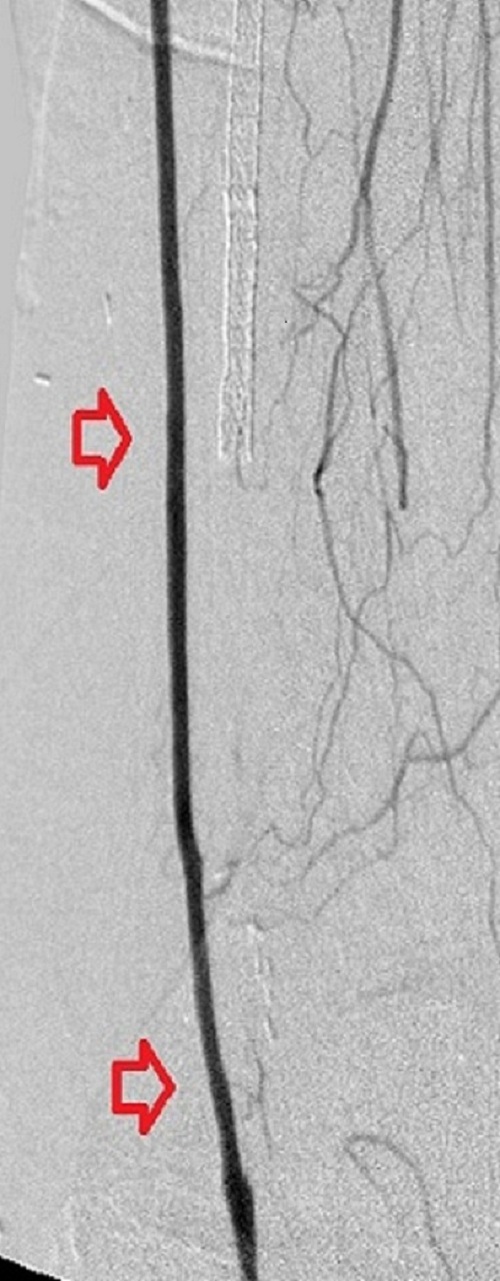

Top panel: Pre-intervention run-off angiogram of the left lower extremity showing, from left to right, irregular left common femoral artery (LCFA) arrowed on the 1st image, absent left superfical femoral artery (LSFA) or any bypass conduit on the 2nd image, sketchy descending collaterals from the left deep femoral (LDFA) that reconstitute a faint shadow of the left popliteal artery, arrowed on the 3rd image. The last 2 images faintly show three-vessel run-off below the left knee. The anterior tibial artery is most opacified, followed by the posterior tibial artery; the peroneal artery peeps through the upper edge of the last image. Note how weakly visible these vessels are due to the poor inflow from above.

When blood flow into or out of a bypass fails, it thromboses and its salvage includes gaining access into it and removing the clot in addition to determining the reason for its failure. Such clot removal may be mechanical, as is frequently the case in acute graft failure, or through thrombolysis, as is the case in later failures. The above images illustrate the later scenario in which the patient presented about 1 year after a left femoropopliteal bypass was fashioned for them. I crossed into the lumen of the bypass conduit from a right common femoral arterial puncture and advanced an infusion cather into it for overnight continuous alteplace infusion following a bolus dose. (I favor 5 to 10 mg of alteplace bolus, followed by continuos infusion at 0.5 mg per hour, in company with fixed unfractionated heparin infusion at 500 units to 600 units per hour after a bolus dose of 3000 units to 5000 units). In this case the bypass proved to be a vein conduit connecting the left common femoral artery, proximally, to the mid popliteal artery, distally, without intimal hyperplasia. The cause of the failure was diminished inflow due to left iliac disease.The final runoff images reveal a three-vessel tibial domain continuous with a near-normal plantar arch.